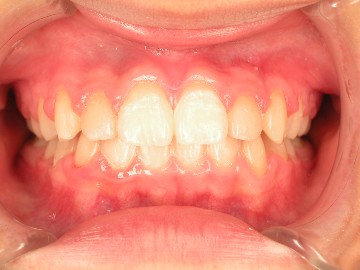

經過一年的矯正後,可見原埋伏齒已拉至正常齒列(圖七),X光可見犬齒的牙根尖發育良好(圖八)。

術前、術後比較

術前 |

術後 |